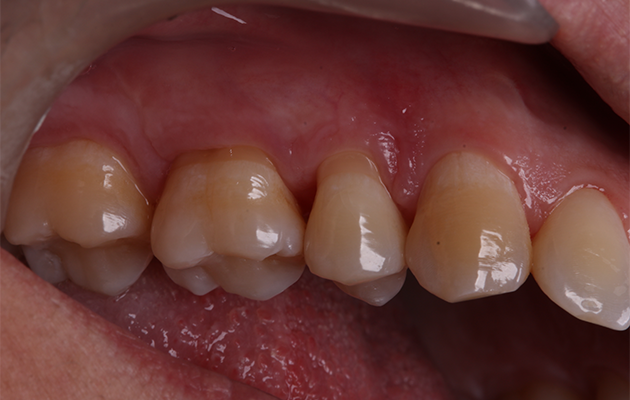

5 | Condição clínica pré-cirúrgica.

22 | Acompanhamento 90 dias.